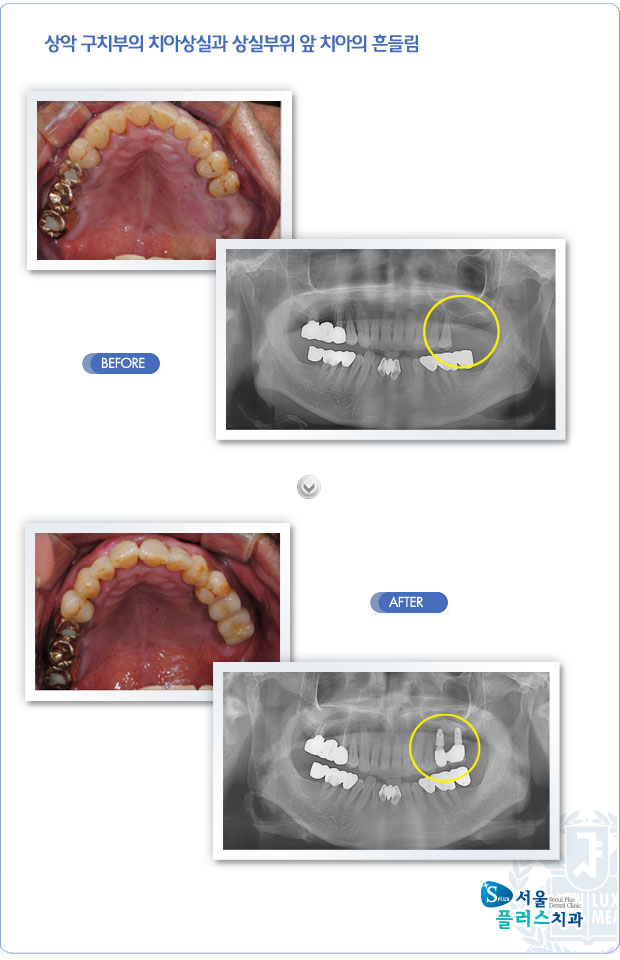

[임플란트] 상악 구치부의 치아상실과 상실부위 앞 치아의 흔들림